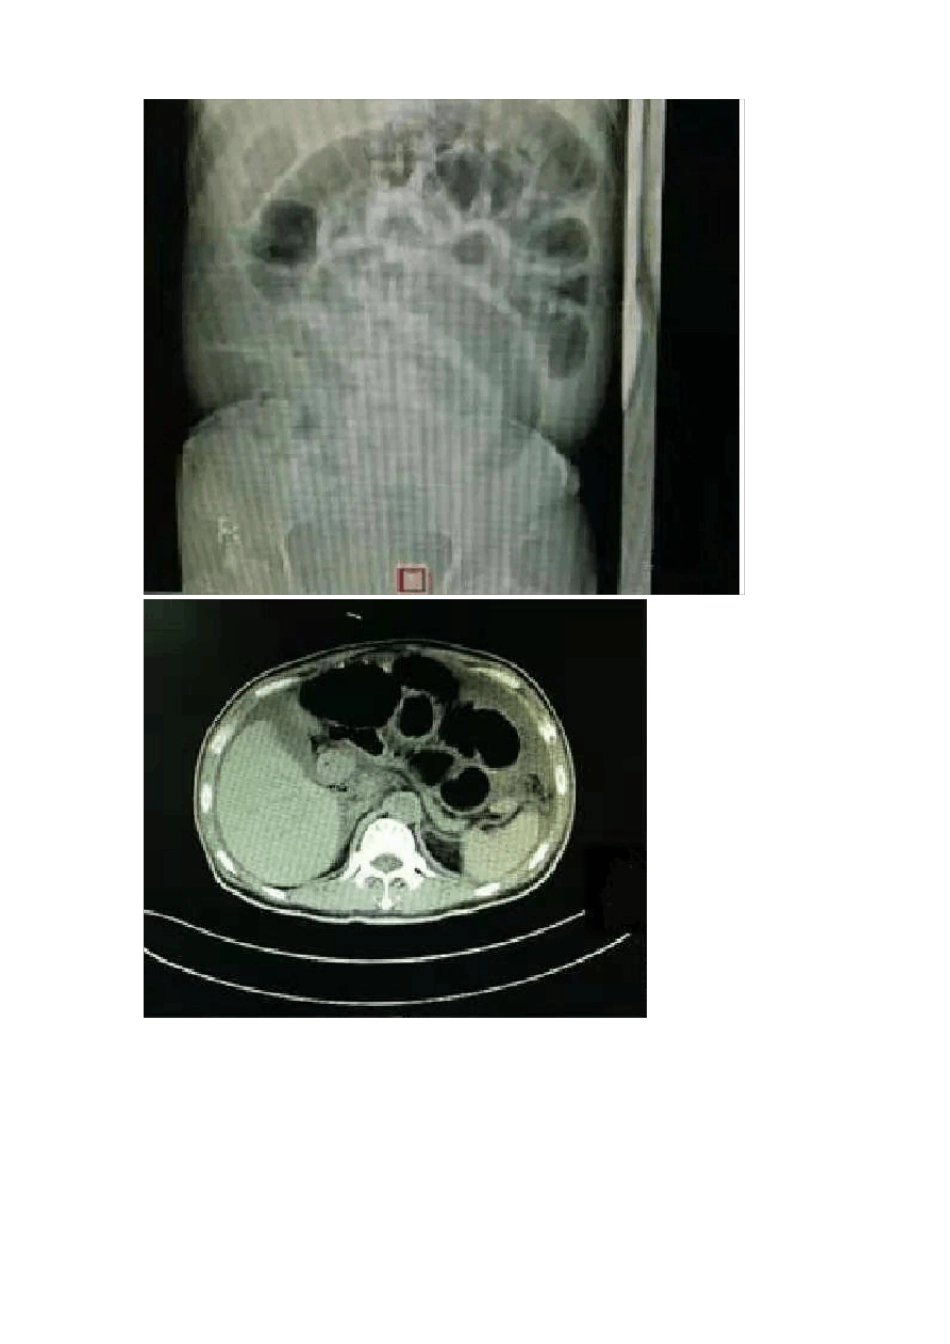

感染性休克患者的麻醉管理【导读】在围术期,多种因素导致的脓毒症易演变为严重脓毒症及感染性休克,合并感染性休克的严重脓毒血症的死亡率高达40%。因此要求临床医生尤其麻醉医生掌握感染性休克的诊断、病理生理变化及治疗,并在此基础上开展多学科的紧密合作,共同做好感染性休克患者的围术期管理,以降低感染性休克患者的围术期死亡率。【病例简介】患者男,54岁,173cm,52kg。主诉∶直肠癌综合治疗后1年半,腹胀、呕吐、便秘1月余。术前诊断:肠梗阻;窦性心动过速;怀疑感染性休克。拟行手术∶剖腹探查术。既往史:2017年9月至12月在外院行化疗,2018年1月腹腔镜下直肠癌根治术+回肠末端双腔造口,2018年5月行回肠造口关闭术。麻醉前访视情况体格检查:患者神志清醒,对答如流,慢性病容,消瘦。体温(T)39.4°C,脉搏(P)152次/分,呼吸(R)26次/分,血压(BP)88/58mmHg,血氧饱和度(SpO2)94%。双肺呼吸音清,未闻及干、湿性啰音及胸膜摩擦音。全腹膨隆明显,皮肤紧张,腹部少许压痛,无反跳痛。双下肢无水肿,神经系统查体未见异常。术前检查心电图(ECG):窦性心动过速,V5-V6r波上升不良。胸片:左肺上叶前段,下叶外基底段轻度炎症。左侧胸腔少量积液。腹部平片:右中上腹见液气平面,左上腹肠管扩张明显。腹部CT∶腹部肠管扩张,腹腔大量积液。术前动脉血气分析循环情况感染性休克诊断标准:脓毒症患者经充分容量复苏后仍存在持续性低血压,需缩血管药物维持平均动脉压(MAP)≥65mmHg且血清乳酸水平>2mmol/L。【问题】1.围术期感染性休克的诊断?2.感染性休克患者的病理生理变化?3.感染性休克的液体复苏?4.感染性休克患者血管活性药物和正性肌力药物应用的时机及药物选择?5.围术期感染性休克激素使用的时机、剂量和持续时间?6.ScvO2值和Lac对感染性休克治疗的指导意义?7.感染性休克麻醉前评估和准备?8.对于感染性休克患者,如何选择麻醉方式及麻醉药物?9.感染性休克麻醉术后转归?(病房或lCU)1.围术期感染性休克的诊断?根据2012年世界上30多种急危重症医学会的专家参与修订,出版于2013年2月的《脓毒症生存运动:治疗脓毒症和感染性休克国际指南》,定义感染性休克(septicshock)为适当补液治疗仍未能纠正的持续性脓毒症引起的低血压;感染性休克的本质:炎症导致紊乱而失调的宿主反应(包含炎症反应和涉及多系统的非免疫性反应)和危及生命的器官功能障碍;当脓毒症发生循环障碍及细胞/代谢异常,继而增加病死率的状态就是感染性休克。当围术期发生感染性休克的病理生理过程可以称为围术期感染性休克。脓毒症引起的低血压(sepsis-inducedhypotension)标准为收缩压(SBP)<90mmHg或平均动脉压(MAP)<70mmHg,或SBP下降40mmHg以上,或低于正常血压的2个标准差,且无其他原因的低血压。感染性休克的临床诊断标准:脓毒症患者经充分容量复苏后仍存在持续性低血压,需缩血管药物维持平均动脉压(MAP)≥65mmHg且血清乳酸水平>2mmol/L,根据这一组合标准,感染性休克的住院病死率超过40%。感染性休克的诊断在脓毒症基础上,对于基础器官功能障碍状态未知的患者,基线的序贯器官衰竭评分(SOFA)评分设定为0,将感染后SOFA评分快速增加≥2作为脓毒症器官功能障碍的临床判断标准。快速SOFA评分(qSOFA)作为院外、急诊室和普通病房的床旁脓毒症筛查工具,以鉴别出预后不良的疑似感染患者(表5-7、图5-9)。qSOFA由意识状态改变、收缩压≤100mmHg和呼吸频率≥22次/分共3项组成,符合2项或以上,即qSOFA评分≥2则为疑似脓毒症。由于SOFA已是重症医学领域常用的评分工具,且简单易行,因此工作组推荐将其作为lCU内脓毒症的临床诊断。而对于怀疑感染的非lCU患者,Seymour等研究提示qSOFA对于住院病死率的预测效度优于SOFA和SlRS,因而可作为患者的非常便捷的床旁脓毒症筛查工具。表5-7序贯(脓毒症相关)器官衰竭评分系统(SOFA)注:儿茶酚胺类药物剂量单位为μg/(kg·min),至少1小时;1mmHg=0.133kPa;氧合指数为PaO2(mmHg)/FiO22.感染性休克患者的病理生理变化?(1)感染、炎症反应与免疫:通常认为发生感染性休克时,致病微生物作用于机体,激活免疫...